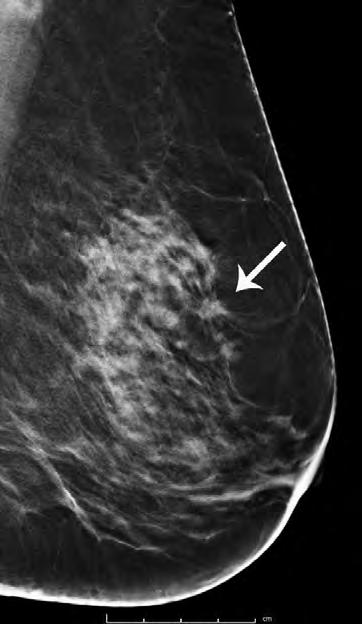

The conscientious process begins with the patient arriving in the clinic, with a complaint that they have found either a lump or abnormal feeling on their body – all of which are common signs of cancer. For example, in a breast cancer clinic, after the patient has reported an issue they have found in their breast, either near their armpit or in the main chest cavity, the doctor conducts a test to deduce whether A) a tumour is present and B) the tumour is malignant and dangerous to the patient.

If the doctor finds signs of a potential malignant tumour, they immediately ask the patient to have either an MRI, PET or CT scan, depending on the size and severity of the tumour that the doctor has detected.

The patient then completes the scan, and the results are analysed during an MDT meeting, where a variety of specific specialists come together to discuss multiple cases, and they decide what next steps should be taken in order to improve the patient’s health.

In one circumstance, a PET scan detected lesions within the breast of a patient, and the conclusion during the MDT meeting was to conduct a biopsy to further analyse the tumour.

Advancements in imaging techniques, such as MRI, CT scans, and PET scans, have complemented traditional dissection methods by providing non-invasive ways to visualize and detect cancers within the body. These technologies have enhanced the accuracy and efficiency of cancer diagnosis.